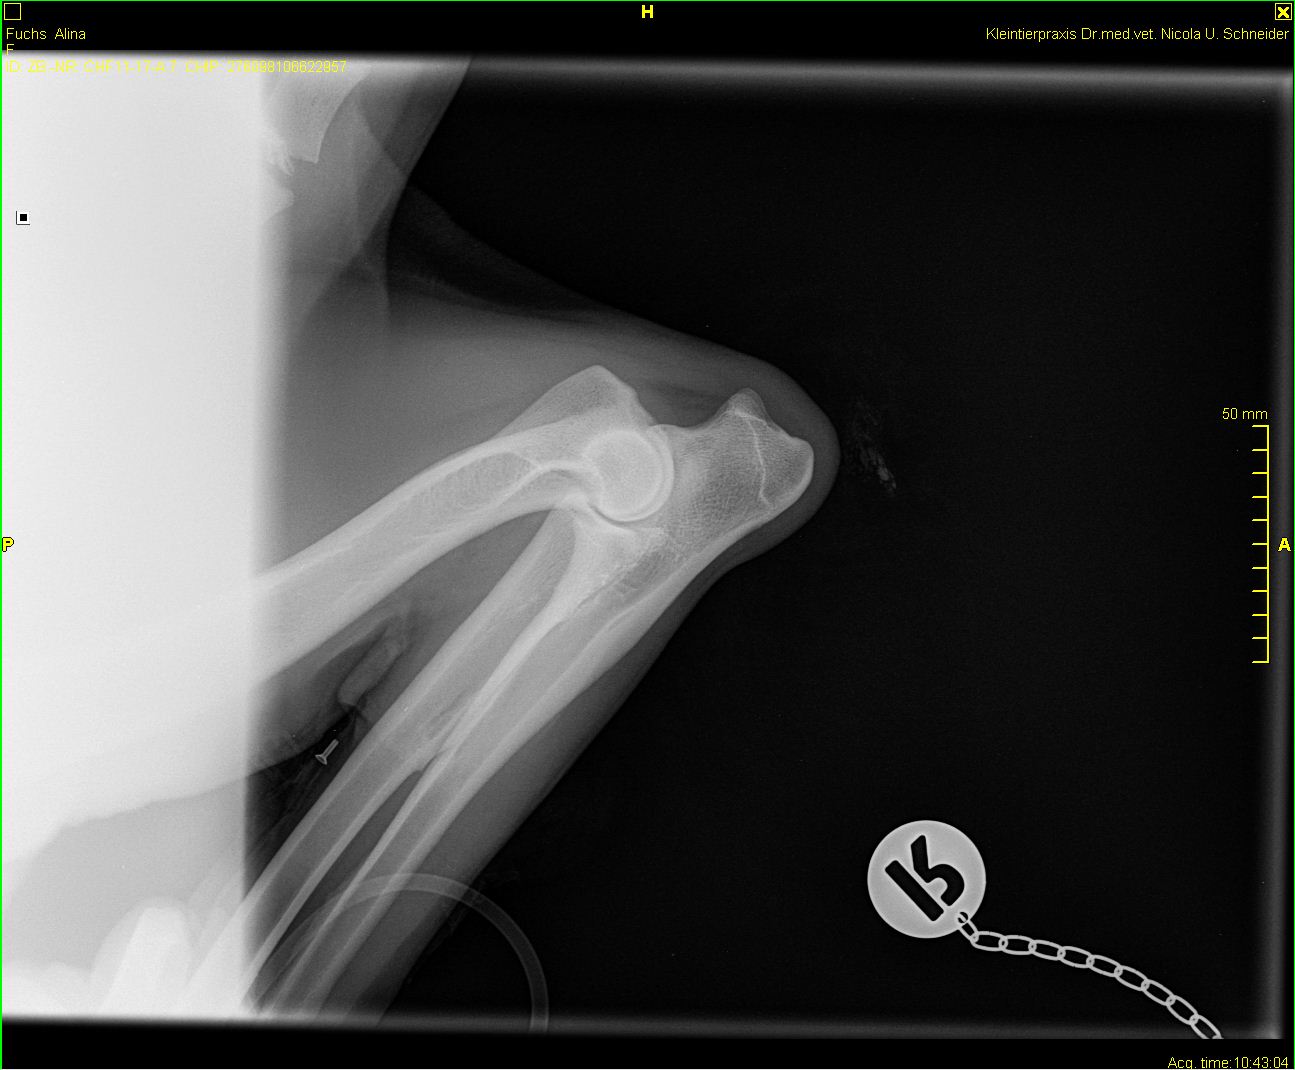

Alina - ED-Röntgen

-Alina-ed-rechts